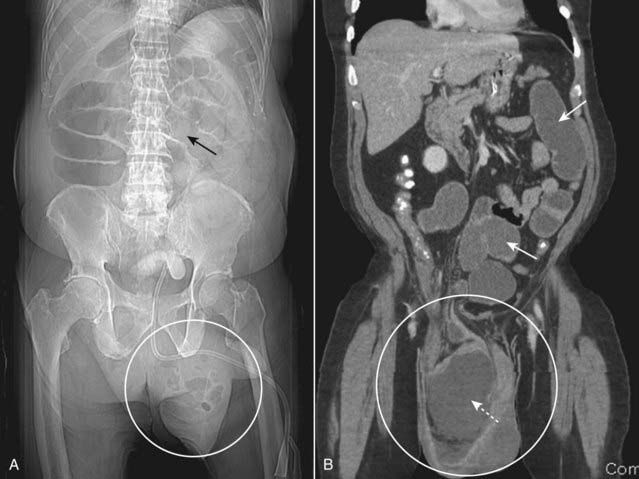

Figure 14-3 Small bowel obstruction from inguinal hernia.

A, The scout image from a CT scan of the abdomen reveals dilated loops of small bowel (solid black arrow) caused by a left inguinal hernia (white circle). Loops of bowel should normally not be present in the scrotum. B, Coronal-reformatted CT scan on another patient shows multiple fluid-filled and dilated loops of small bowel (solid white arrows) from a right inguinal hernia (white circle) containing another dilated loop of small bowel (dotted white arrow).